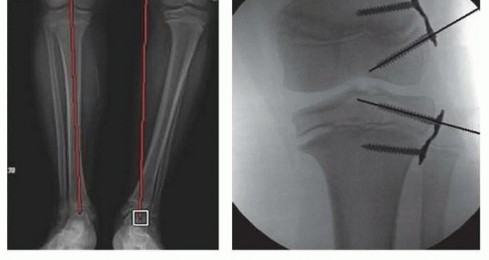

- The mechanical axis represents the weight-bearing alignment of a bone or an extremity in either the coronal or sagittal plane. It is a straight line connecting the proximal and distal extent of the bone regardless of its anatomic alignment. For example, the normal mechanical axis of the lower extremity in the coronal plane is a straight line from the center of the femoral head to center of the distal tibia and

- passes through the middle of the knee (FIG 1).14

- FIG 1 • A. The mechanical axis is a straight line drawn on a full-length, standing AP, or lateral radiograph of the lower extremity connecting the center of the femoral head to the center of the distal tibia. The normal angles for LDFA, MPTA, and LDTA will assist in identifying the location of deformity in the coronal plane, and PDFA, PPTA, and ADTA likewise will locate deformity in the sagittal plane. B. Dividing the knee into zones, the mechanical axis should pass through the central one-third of the joint. Deviation into zone 2 or 3 indicates deformity which may require surgical intervention.

- The mechanical axis is used to assess coronal and sagittal plane deformity and guide surgical correction to restore a normal weight-bearing alignment. Sagittal plane deformity can also be manipulated to improve the amount of extension at the knee or dorsiflexion at the ankle.

- ### Mechanical and anatomic axis of lower extremity (see FIG 1A)15

- Lateral distal femoral angle (LDFA) = 87 degrees Medial proximal tibia angle (MPTA) = 87 degrees Posterior distal femoral angle (PDFA) = 83 degrees Posterior proximal tibia angle (PPTA) = 81 degrees

- ### Lateral distal tibia angle (LDTA) = 89 degrees Anterior distal tibia angle (ADTA) = 80 degrees

- ### Center of rotation of angulation (CORA) is the location of deformity in a long bone. If a single point of deformity exists, the point of intersection between the proximal mechanical axis and the distal mechanical axis is the CORA and it should correspond to anatomic deformity. If a constructed CORA does not correspond with obvious anatomic deformity, another deformity must exist. Therefore, deformity correction should occur at the

- CORA to restore the mechanical axis.14